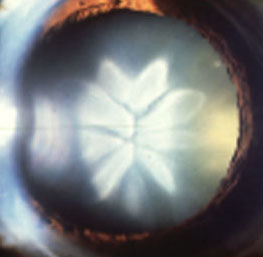

In a general clinic, you come across the following lens changes. Look

at each picture and answer the questions.

Suggest two possible causes for this lens appearance. Does it affect the

vision?